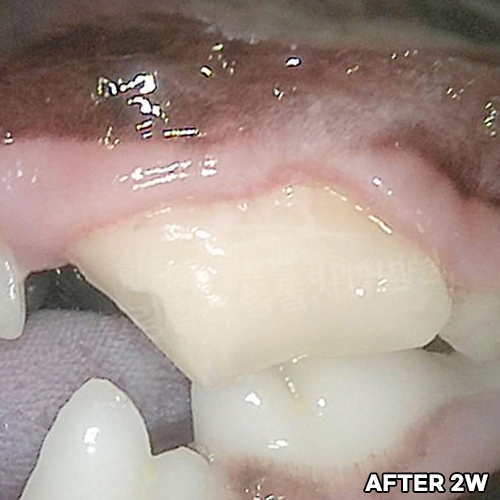

웰시코기의 아주 심한 파절치아를 강아지치과에서 수술하고 1년 뒤에도 잘 씹어요~!! - 동물치과 힐링힐스 -